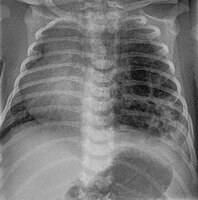

Three quarters of affected people are asymptomatic. About 25% develop cyanosis, pneumothorax, and show signs of increased breathing difficulty (tachypnoea and intercostal retractions).

At examination, they may show hyper-resonance at percussion, diminished vesicular murmur and an asymmetrical thorax.